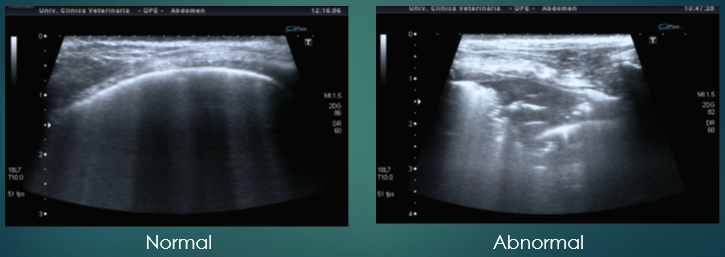

Diagnosis - Ultrasonography

More common in emergency situations to quickly check for fluid

Not usually in a standard workup